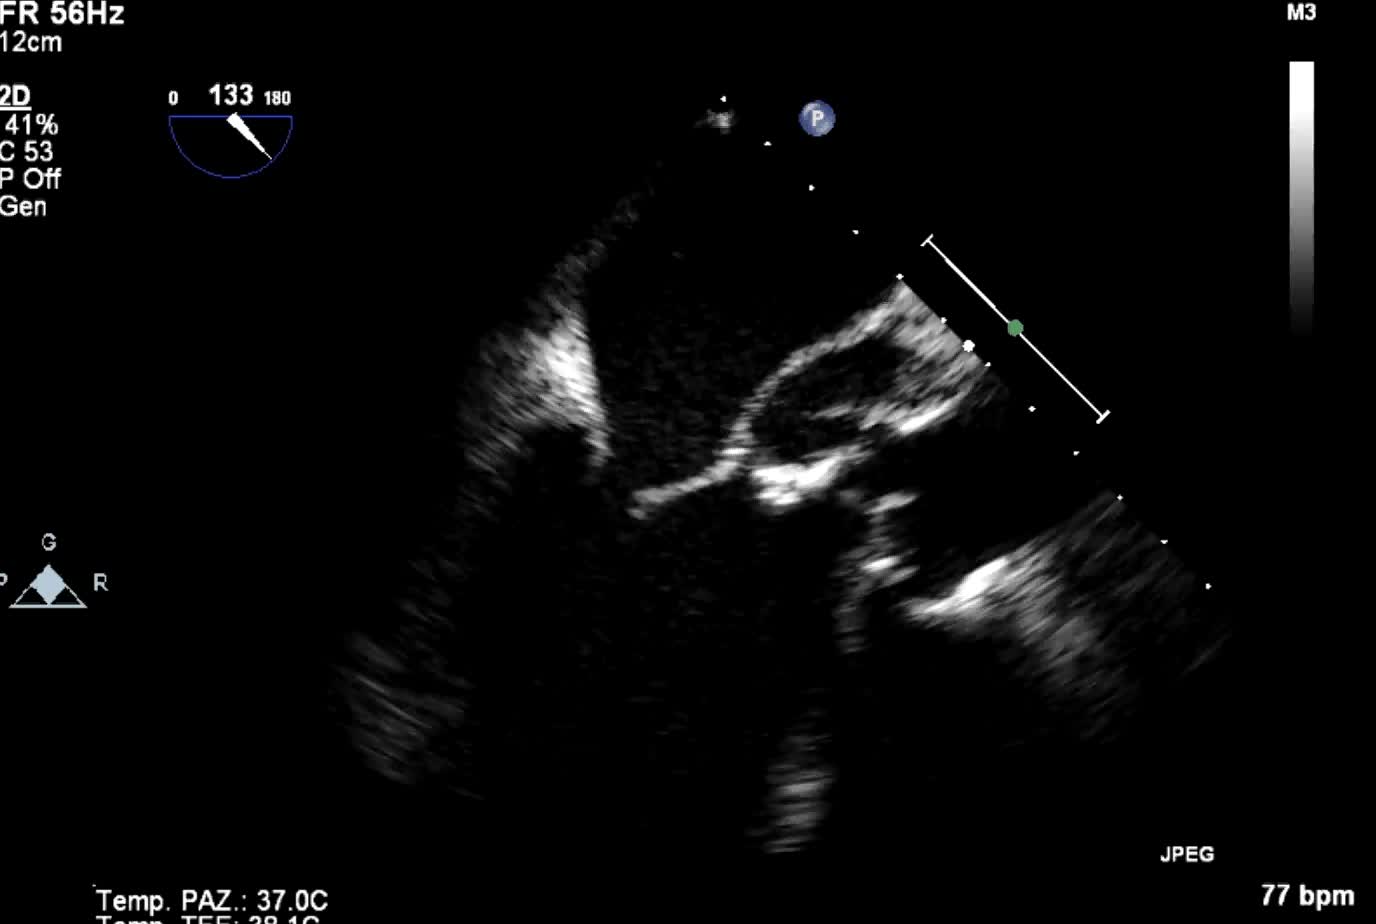

Endocardite infettiva della valvola tricuspide

Autore:

Andrea Barbieri